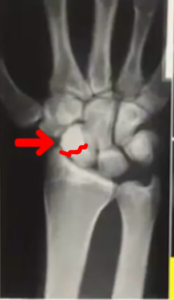

実際のレントゲン写真。→の部分が舟状骨骨折部位。

この舟状骨骨折は見逃されやすい骨折です。

特徴は、腫れが少なく見逃されやすい。放置すると治りにくいなどがあります。

血流が乏しい場所でもあり、治療をせずに放置すると「偽関節」(骨がくっつかない状態)になることもある要注意の骨折です。